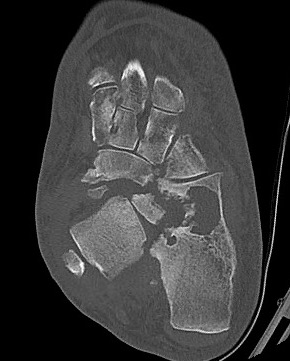

Midfoot dissolution, coalescence and reconstruction

Brodsky Classification

| Type 1 Midfoot (60%) | Type 2 - Hindfoot (30%) | Type 3 (10%) |

|

Metatarsocuneiform and naviculocuneiform

Collapse of the medial longitudinal arch with rocker bottom foot |

Subtalar joint, talonavicular, calcaneocuboid

More unstable than type 1 Require longer periods immobilisation |